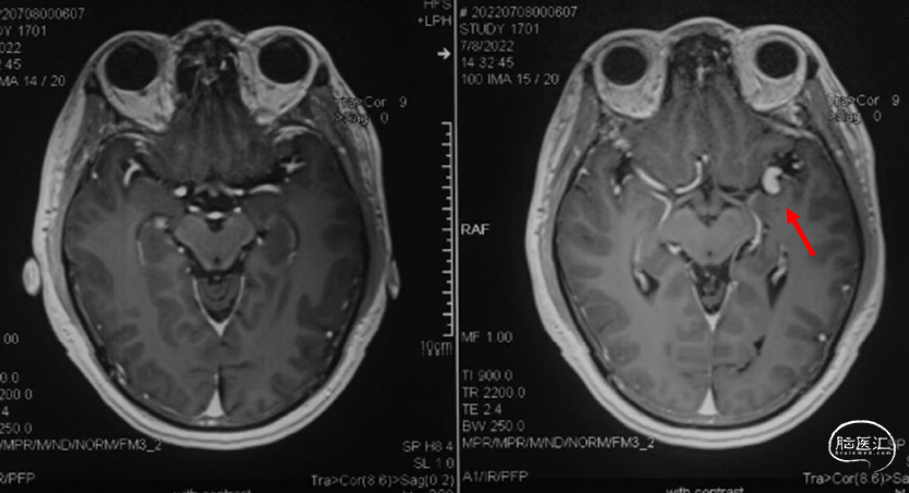

术前头颅核磁:T2象可见血管流空影,增强序列见侧裂区异常血管影。(07-08)

术前头颅MRA示:L-MCA分叉处夹层动脉瘤(07-12)。